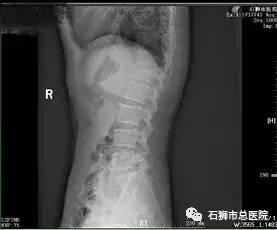

患者,女,89岁,以"摔伤致腰背部肿痛,活动受限5天"为主诉入院。入院诊断:1.腰2椎体压缩性骨折;2.骶椎骨折,3.高血压病(2级高危)。

考虑患者近九十岁高龄,常规手术风险难以耐受,且椎体后壁破碎,手术风险极高,经科室内讨论,拟行经皮椎体球囊扩张成形术,术中为进一步减少手术时间,减少手术风险,降低骨水泥经后壁进入椎管风险,予改良行单侧经皮椎体球囊扩张成形术。

手术 · 前